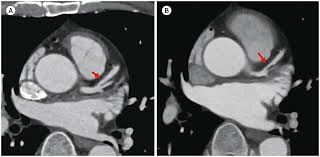

3. 진단 방법 – CAC 스코어

- 비침습적 **관상동맥 칼슘 스캔(칼슘 스코어 CT)**로 Agatston score 산출 :contentReference[oaicite:6]{index=6}.

- 0 = 이상 없음, 1–99 = 경증, 100–399 = 중등도, ≥400 = 중증으로 분류되며, 점수가 높을수록 심혈관 위험이 증가합니다 :contentReference[oaicite:7]{index=7}.

- 중등도 이상일 경우 관상동맥 협착 위험이 높으며, 추가 정밀검사 및 적극 치료가 필요합니다 :contentReference[oaicite:8]{index=8}.

- CT 스캔은 빠르고(약 15분), 고해상도이며, 진단·예후 판단에 유용합니다 :contentReference[oaicite:9]{index=9}.